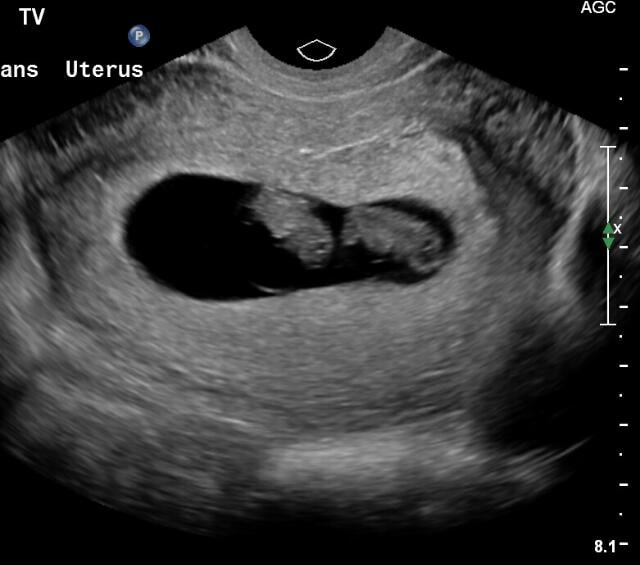

Автор вот двойня однояйцевая на сроке 8 недель Изображение

однозначно один на этом снимке

На этом фото один.